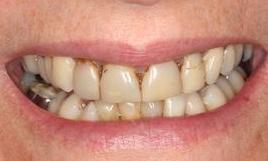

This before and after showcases a comprehensive dental restoration involving root canal therapy, the placement of dental crowns for structural integrity and aesthetics, as well as a full upper denture to restore function and appearance.